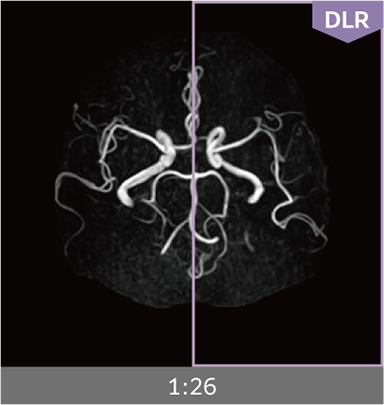

Combining high-speed imaging technology with Deep Learning reconstruction technology*3, Advanced Reconstruction with Deep Learning Synergy DLR, enables shorter exams and reduces image noise.

Images can be obtained at high speed by combining two proprietary technologies: IP-RAPID, which reduces imaging time while maintaining image quality, and Synergy DLR, which uses deep learning technology*6 to improve image quality

Under-sampling reduces imaging time, and iterative reconstruction with IP-RAPID reduces noise and artifacts.

In addition, Synergy DLR, an image reconstruction technology utilizing deep learning technology, further eliminates noise and produces images that are easier to use in making a diagnosis.